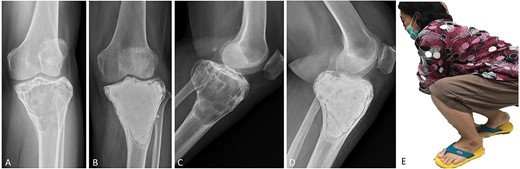

(A, C) Case no. 6: male, 15 years of age with GCTB at the distal femur without subchondral bone involvement, Campanacci grade II. (B, D) Radiograph at 67 months after extended curettage with hydrogen peroxide, phenol, and cementation. (E) MSTS score 100%.

Surgical procedures were performed by two orthopedic oncology surgeons using the same surgical technique. In all cases, GCTB was confirmed by clinical data, plain radiography and magnetic resonance imaging (MRI), as well as histopathologic examination before and after surgery. Whether a medial or lateral approach was employed depended on tumor location. A large cortical window equal in size to the tumor area was created to provide visualization of the entire tumor cavity, and intralesional curettage of the tumor was performed. If the tumor extended into the soft tissue, the entire pseudo-capsule was dissected circumferentially and excised. A high-speed burr was used to extend the cavity by at least 2 mm to remove the residual tumor in all cases except those in which the lesion was in subchondral bone and cartilage. Hydrogen peroxide is the preferred local adjuvant agent at our institution, but phenol was applied along the cavity wall using gauze in three cases, and argon beam coagulator was applied in six. After the application of local adjuvant, the irrigation cavity was rinsed with saline solution. If the tumor involved subchondral bone or cartilage, hydroxyapatite bone substitution was applied 5–10-mm above subchondral bone to prevent complications from allograft and donor-site morbidity of the autogenous bone graft. We defined subchondral bone involvement as tumor location <5 mm from joint cartilage. Every part of the remaining cavity was filled with PMMA without implant augmentation or internal fixation (Figs 1–4). The large cortical window was left open with cement in most of the cases in which the cortex was destroyed by the tumor.